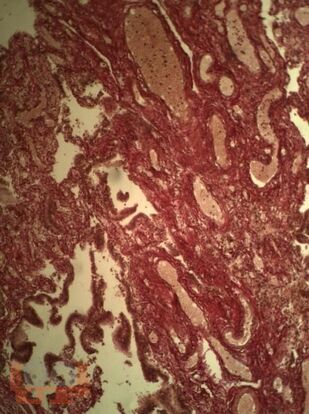

В монографии изложены данные отечественных, зарубежных авторов, результаты собственных исследований, посвященных причинам и механизмам апоплексии яичника у женщин и методам реабилитации для предупреждения рецидива заболевания. Представлены собственные результаты клинико-лабораторных, инструментальных методов исследования, а также опыт применение квантовой терапии в раннем послеоперационном периоде у пациенток с апоплексией яичника.